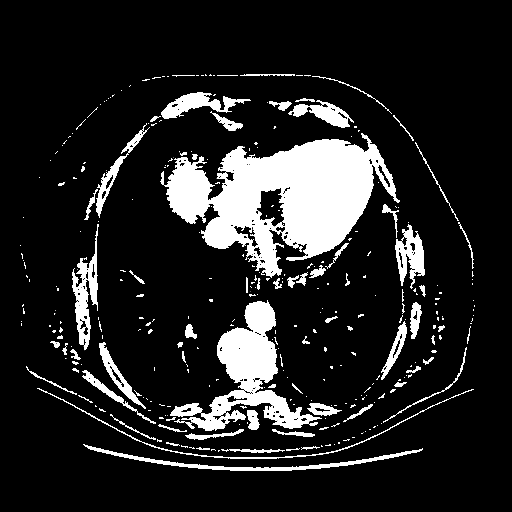

Reconstructed NATIVE CT scan (cycle consistency)

Full window (WL 1023.5, WW 4095 β†’ Low βˆ’1024, High +3071)

Actual HU range: [-1024.0, 3071.0]